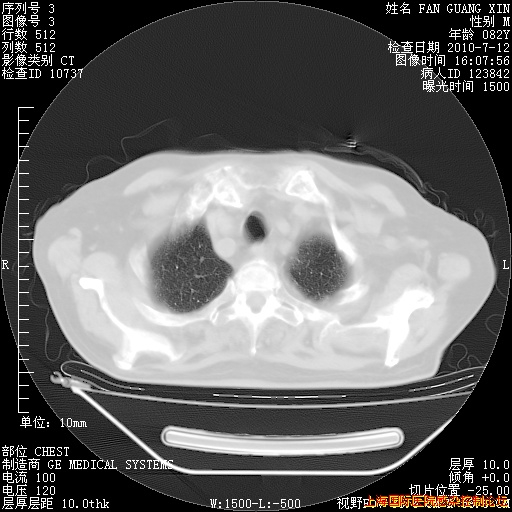

今天复查CT

今天CT

整整相隔30天的肺部CT好像有所好转啊。甲强龙减量第3天,需要观察体温。

海管,自昨日你和我通完话后,不知您岳父消化道症状有无缓解?体温怎样?阅读7.12日胸部ct,个人认为目前激素治疗是有效的,甲强龙减量是适宜的。因在抗痨治疗,需密切观察肝功、肾功能和血常规。不过,老年、长期住院和大量使用激素,很担心菌群失调发生